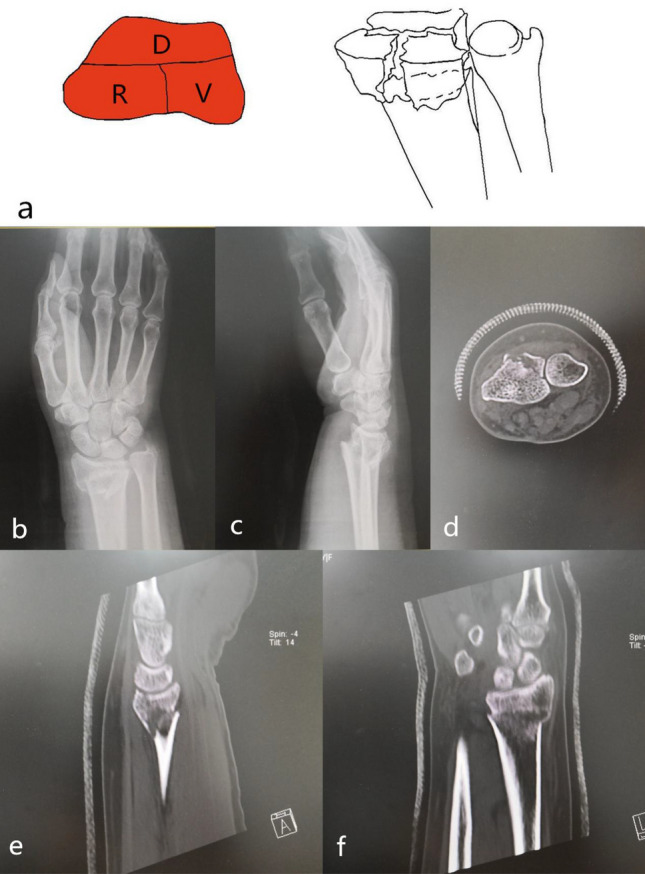

Single fracture of the radial part (1-R): The radial part was composed of the radial styloid process and the palmar hem of the scaphoid fossa. A tough radial wrist ligament was attached around these structures. These structures ensured the flexible movement of the wrist with stability. The fracture was characterized by avulsion violence, causing the radial styloid process to shift to distal and ulnaris sides; While bending + compression violence was the leading cause, radial styloid process was shifted to intact side and rotation displacement due to the pull of the brachioradial muscle. Steps appear in radiocarpal joints. The injury mechanism is avulsion or bending + compression violence. The only surgical approach for reduction and fixation is the radial approach. The processus styloideus radii plate or screw was selected for fixation (Fig. 4).

Figure 4.

Distal radius fracture 123 classification A3.